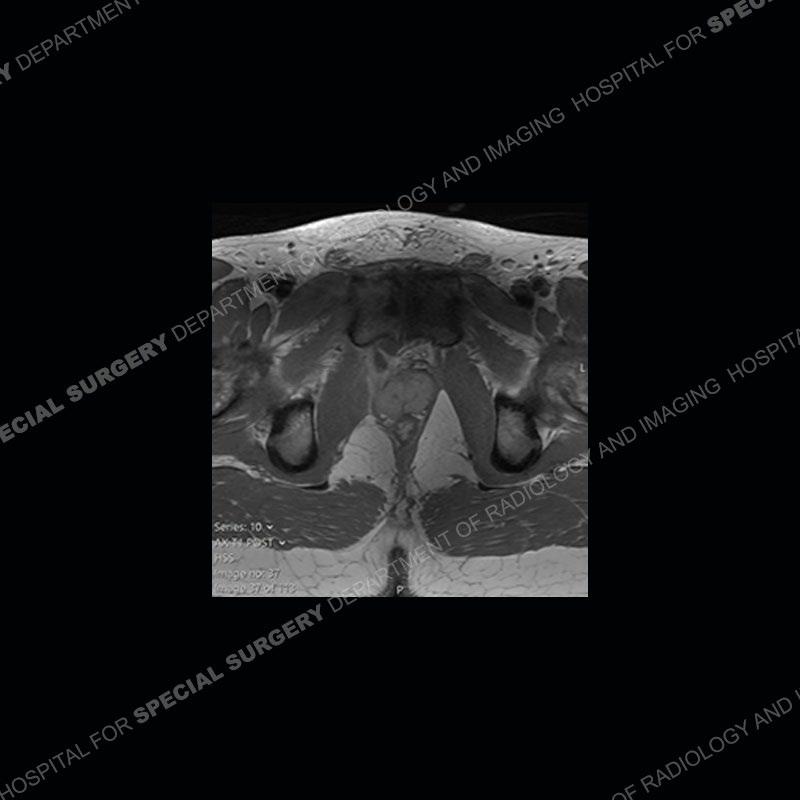

Radiographs did not demonstrate any clear abnormality. The MRI shows markedly abnormal signal of the right superior pubic ramus and abnormal signal/”mass” extending into the adjacent soft tissue. The inferior articular surface of the ramus showed what was thought to be bony destruction. CT examination shows a destructive process of the right superior pubic ramus.

Subsequent MRI in a very short time interval shows markedly increased abnormality of the ramus and increased edema and “mass” of the soft tissue. Post contrast imaging shows multiple, rim enhancing collections of the soft tissue and similar albeit less conspicuous enhancing collection of the ramus.